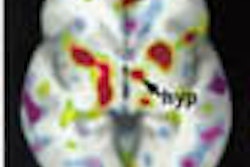

"With that in mind, the purpose of this study was to determine if sequential PET scans identified areas of increased metabolic activity after localized radiation therapy for primary lung cancer," Cohen said.

The team retrospectively reviewed the records of 16 patients with biopsy-proven lung cancer who had undergone FDG-PET imaging both before and after radiation therapy. Only patients who had undergone localized radiation treatment with shielding of uninvolved areas were included, from records gathered over a period of 11 months.

"Seventy-five percent of the patients showed uptake in four patterns, 25% of the patients showed no changes after radiation, and all patients showed tumor regression," Cohen said.

The two most common patterns were contralateral peripheral pleural uptake in five patients (31.2%), and ipsilateral peripheral pleural uptake in 5 patients (31.2%). There was also bilateral peripheral pleural uptake in 1 patient (6.2%), and diffuse background uptake in 1 patient. Three patients showed no increased uptake (18.8%), and only one patient developed clinically significant pneumonitis, Cohen said.

"What we found is that increased metabolic activity in PET scans may be shielded in non-irradiated areas after localized radiation therapy. We don't know if this shows increased lung toxicity or what this uptake represents," Cohen said.